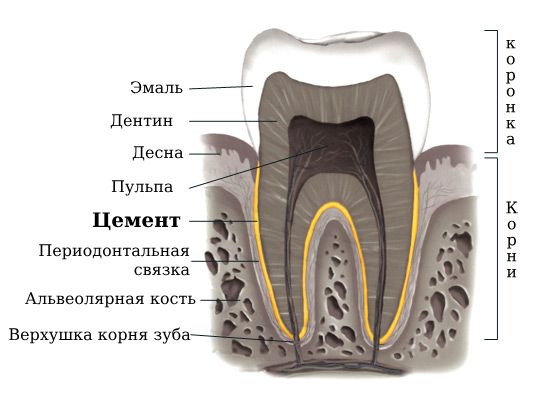

Цементома (Cementoma) — это доброкачественное новообразование в костях челюсти, которое развивается из клеток цемента зуба [1].

Цемéнтом называют минерализованную ткань, которая покрывает корень и шейку зуба тонким слоем, помогая ему плотно закрепиться в челюсти.

Расположение цемента, из которого образуется цементома